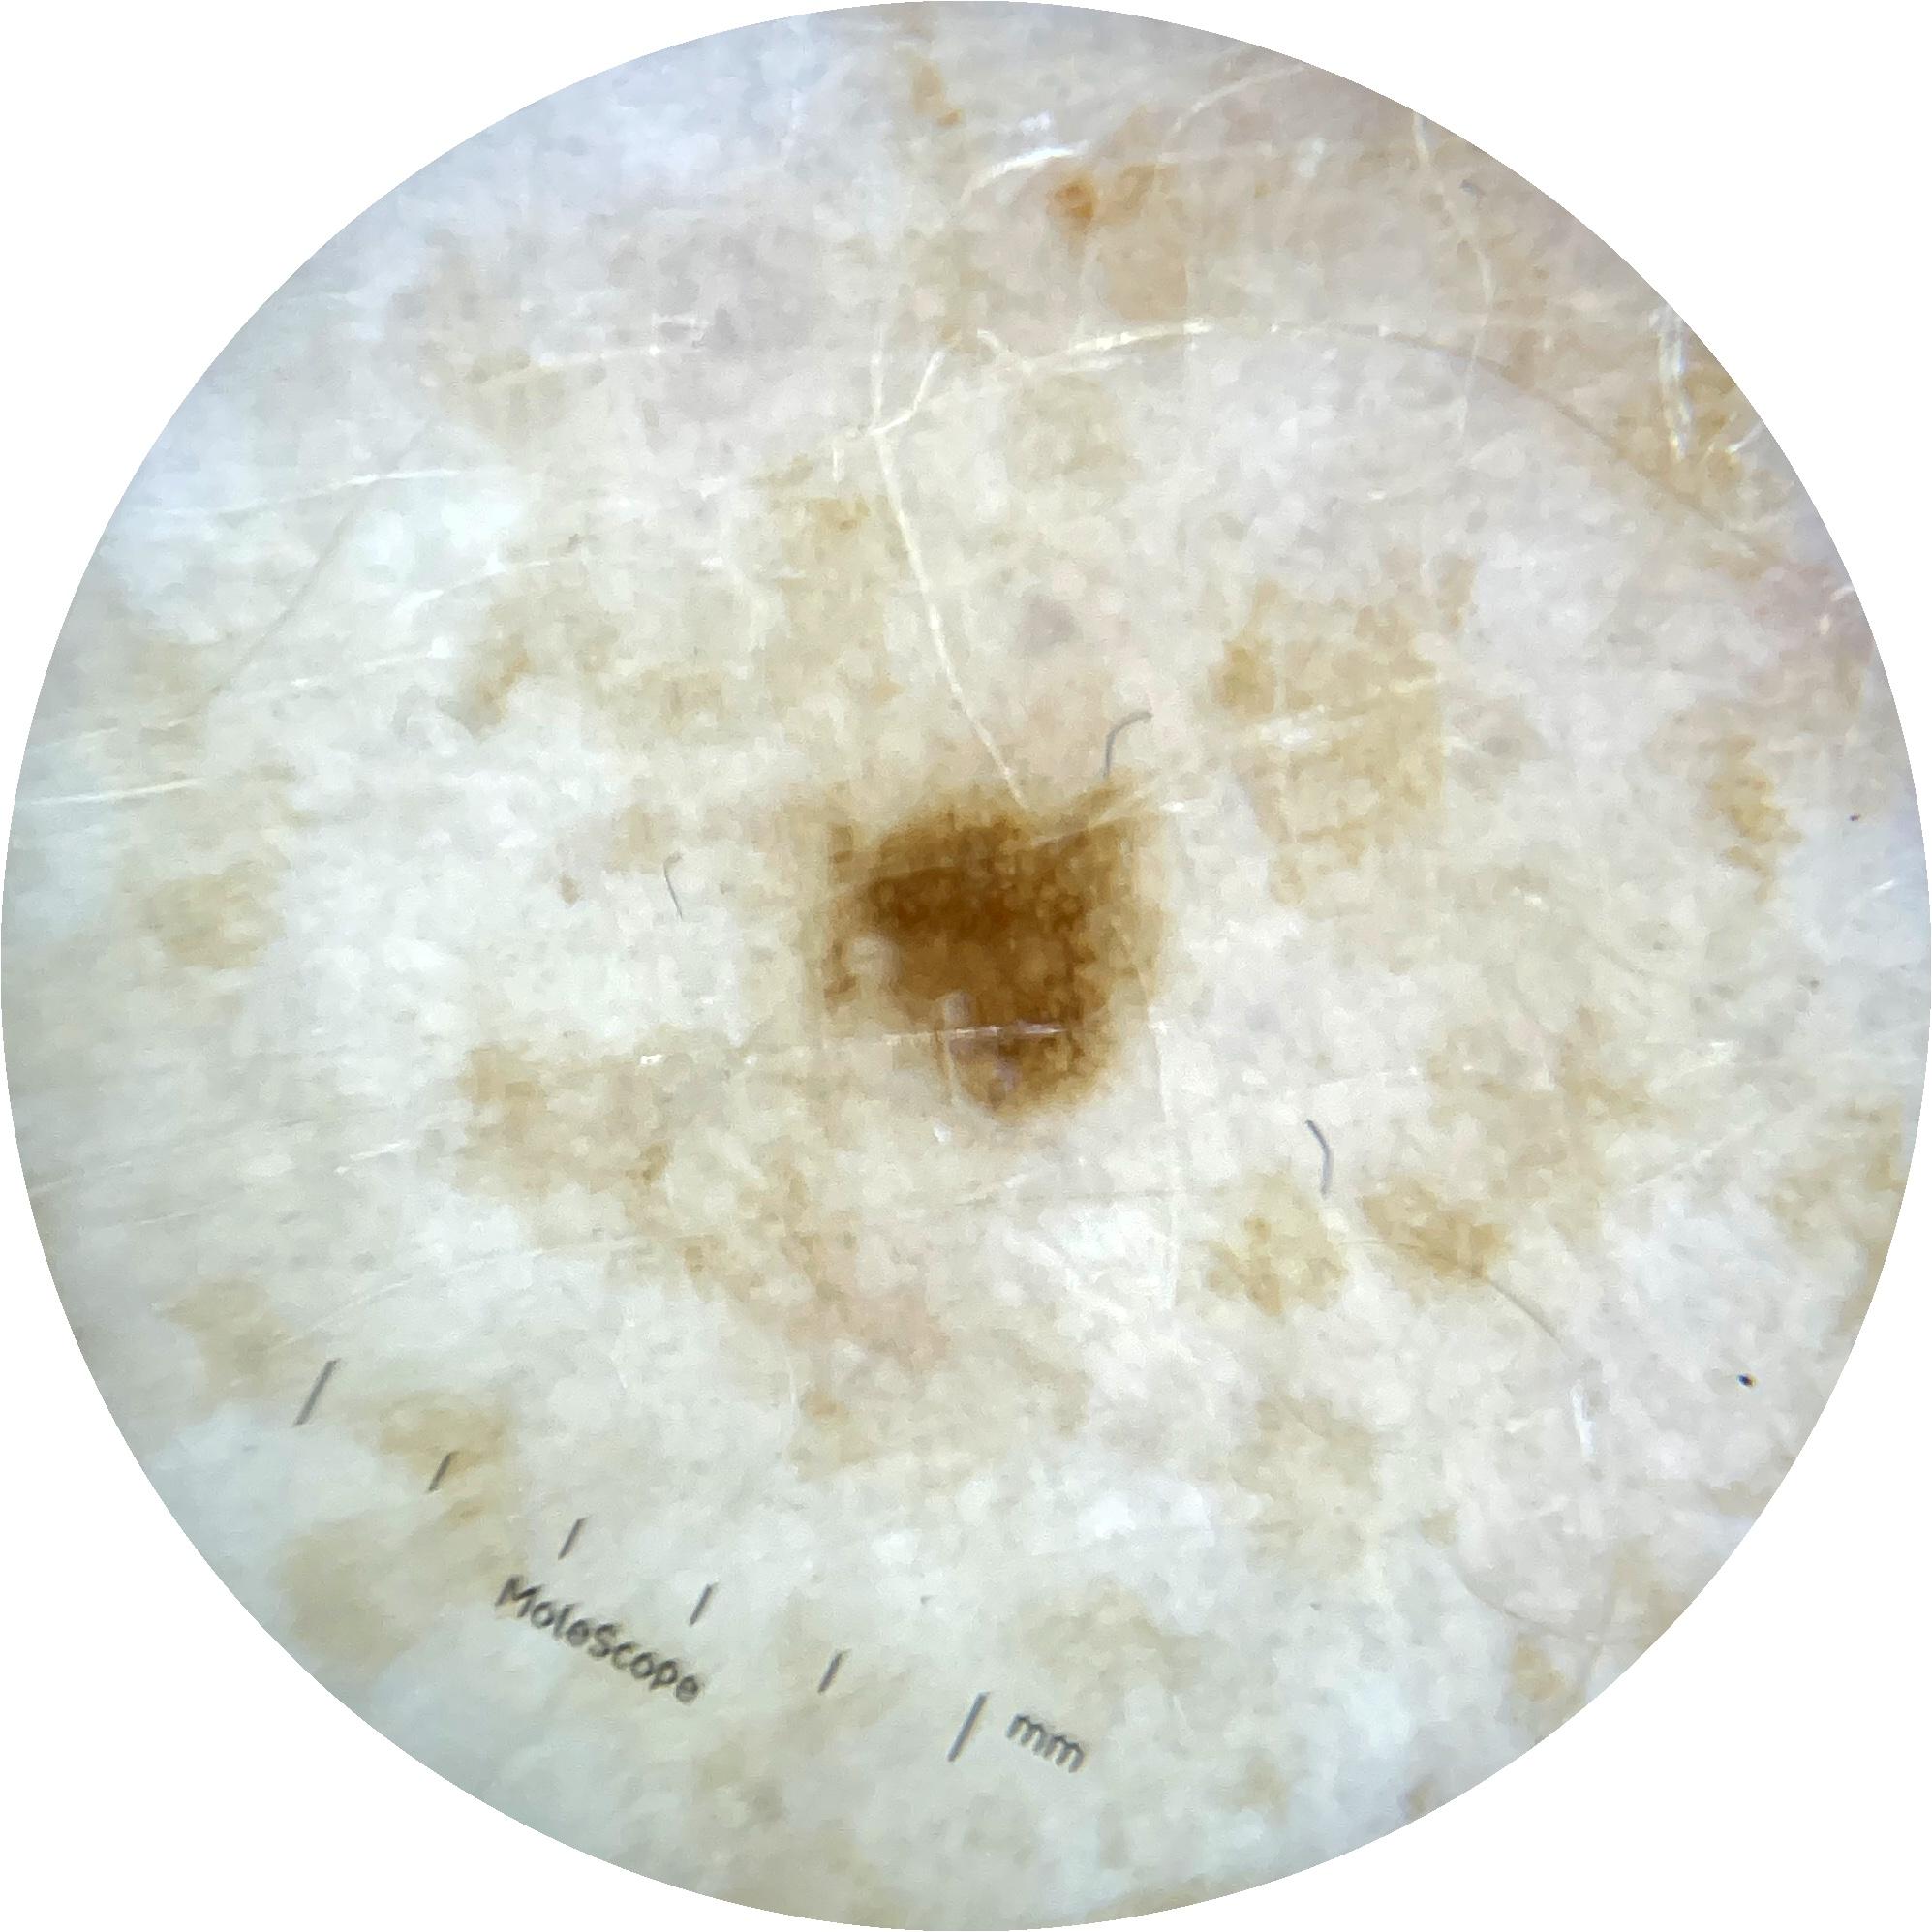

ISIC_9785574

Field Value

acquisition_day 148

age_approx 45

anatom_site_1 Head and neck

anatom_site_general head/neck

diagnosis_1 Benign

diagnosis_confirm_type single image expert consensus

image_type dermoscopic